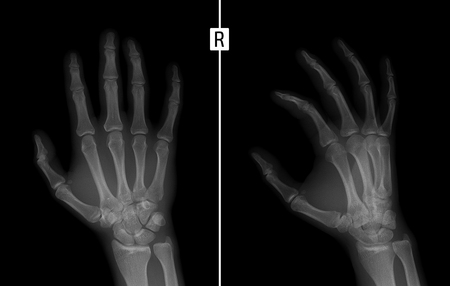

手の X 線写真 右手の第 2 指基節骨の基盤の破壊を示しています の写真素材 画像素材 Image 78162464

てX線像で骨嚢腫のようにみえる 6関節破壊変形骨破壊に関節支持組織の破 綻が加わり特徴的な変形が各関節に生じる 7関節強直骨軟骨破壊の結果関節は線維 性ないし骨性に癒合する手根部や足根部な どに出現することが多い.

X線画像上の関節破壊. Van der Heijdeらによると関節リウマチ患者さんの約70が3年後にはX線画像において関節破壊を示していました 左の図からは発病後1年間の関節破壊が急に進み2年目3年目は進行の速度がやや低下することが示されています. ④画像診断として主に単純x線写真を用います 場合によってCTMRIなどを使用します 変形性股関節症の場合は単純X線写真にて関節裂隙臼蓋と大腿骨頭の隙間の狭まり軟骨下骨の骨硬化像骨嚢胞骨棘形成の程度を評価して関節症の進行具合を確認します. 046 技術解説 X線非破壊検査とは X線非破壊検査とは医療で用いられている.

X線を使った非破壊検査はさまざまな 分野の製品検査や保守に用いられています ここではX線非破壊検査の概要と試験に あたってのポイントを紹介します 6 Tiri News 2010 vol. 手足の X線写真を用いて関節リウマチ患者の関節破壊の進行度を評価す る手法です sharp scoremTSSのベースラインからの変化量により評価したエックス線画像上での関節破壊の 進展が有意に抑制されました024 vs.